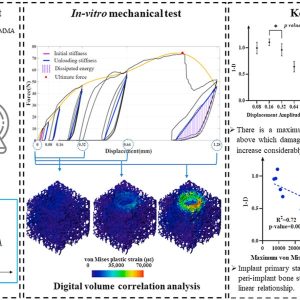

اندازهگیری آسیب استخوانی ناشی از بارگذاری-باربرداری شبه استاتیک برای بررسی پایداری ایمپلنتهای دندانی: استفاده همزمان آزمونهای برونتنی، تصاویر میکرو سیتی و همبستگی حجمی دیجیتال

نویسندگان: ستاره خورشیدپرست، پدرام اخلاقی، غلامرضا روحی و حمیدرضا باریکانی چکیده:پایداری اولیه ایمپلنتهای دندانی، درگیری اولیه مکانیکی میان ایمپلنت و استخوان مجاور است. ایمپلنت و